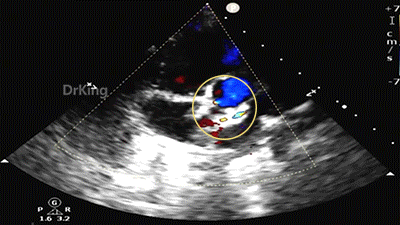

锁定后,主动脉短轴切面显示封堵器呈Y字型抱住主动脉根部。

主动脉短轴切面显示封堵器呈Y字型抱住主动脉根部,夹持稳定。

封堵器形态良好,未见分流,封堵成功。